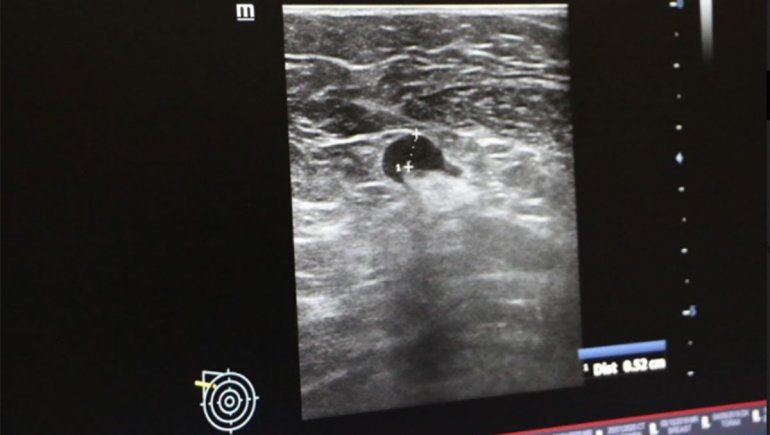

“Hemos visto en nuestras prácticas diarias, en algunos casos de pacientes que se han vacunado, ganglios axilares aumentados de tamaño y con engrosamiento de la cortical”, explicó Lancioni.

“Se han realizado estudios donde advertimos características que han llamado la atención. En un primer momento uno tiende a relacionarlas con alguna patología mamaria, pero analizando y teniendo conocimiento del estudio internacional de expertos, difundido en las últimas semanas, se interpretan estos resultados en relación a la pos vacunación”, agregó la médica especialista en diagnóstico por imágenes.